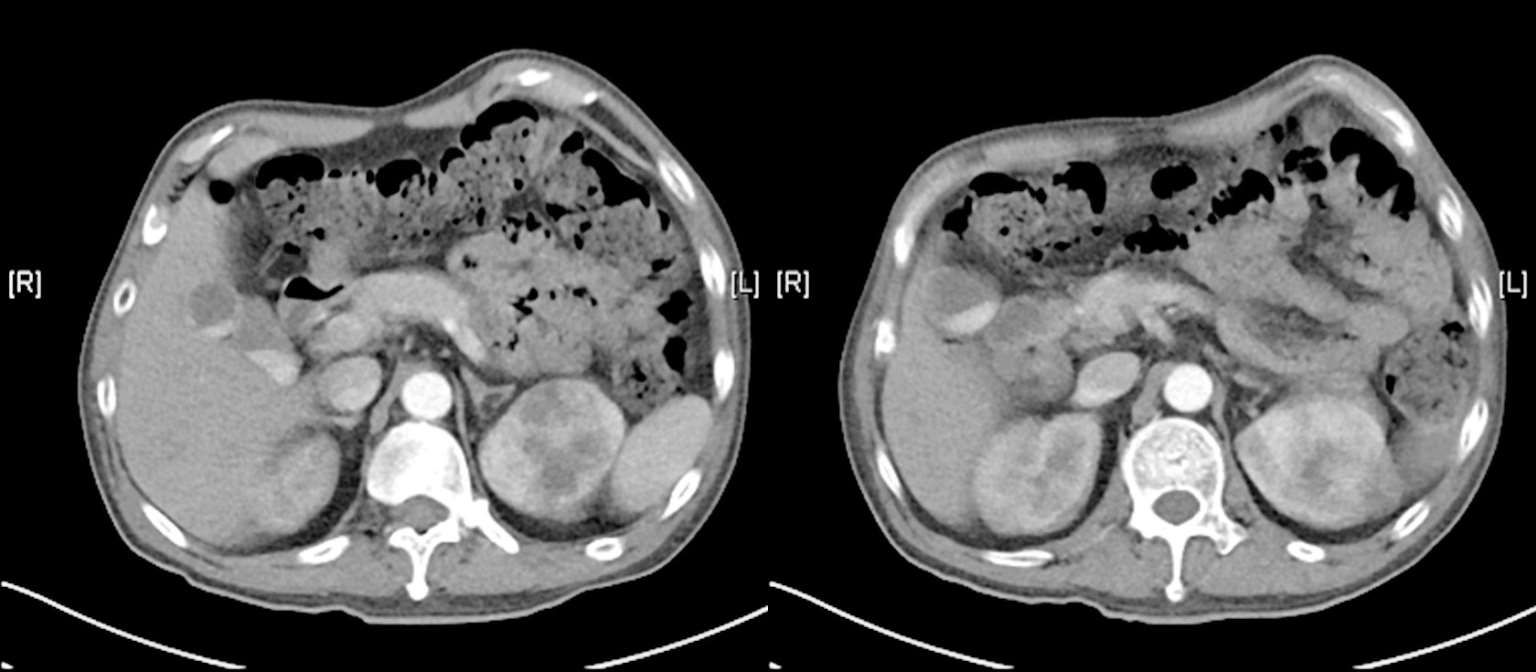

7月30日患者行上腹部增强CT(图2-6),发现肝脾的低密度影已几近消失不见,但回报左肾占位性病变,考虑肿瘤可能。7月30日复查血T-SPOT. TB 仍为阴性。入院治疗两周后8月3日复查腰穿,压力220 mmH 2 O,脑脊液白细胞344×10 6 /L(↑),多核细胞32%,单核细胞68%,脑脊液糖2 mmol/L( ↓),同步血糖5.8 mmol/L,脑脊液蛋白质4 543 mg/L(↑),脑脊液氯106 mmol/L(↓)(表2-1)。脑脊液隐球菌荚膜抗原乳胶凝集试验及培养仍为阴性。此次脑脊液白细胞及蛋白质较前进一步升高,糖进一步下降。虽然此时患者体温已降至正常,但8月7日复查头颅增强MRI(图2-7)见颅内多发异常环形强化灶,部分病灶较前似有所增大,肺部CT平扫却见肺部病灶较前明显吸收减少。同时8月7日第二次脑脊液二代测序回报再次测得中间链球菌,序列数106。

图2-6 2018年7月30日上腹部增强CT

图2-7 2018年8月7日头颅增强MRI及肺部CT平扫